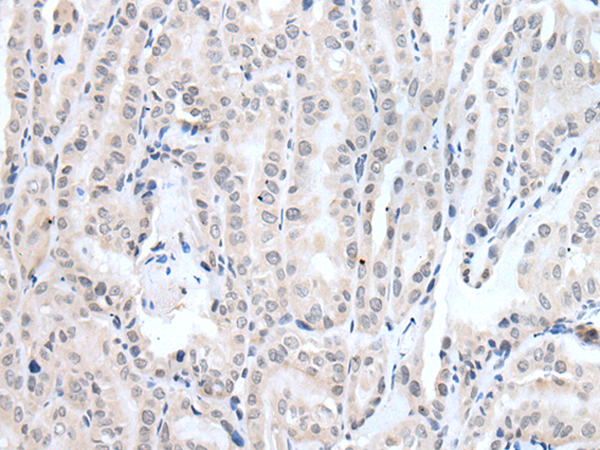

分类: 科研抗体货号: P12771别名: LERN1; MRT64; LRRN6A; UNQ201应用: IHC反应种属: Human, Mouse